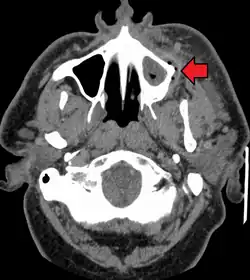

Dental caries can also cause bad breath and foul tastes.[16] In highly progressed cases, an infection can spread from the tooth to the surrounding soft tissues. Complications such as cavernous sinus thrombosis and Ludwig angina can be life-threatening.[17][18][19]